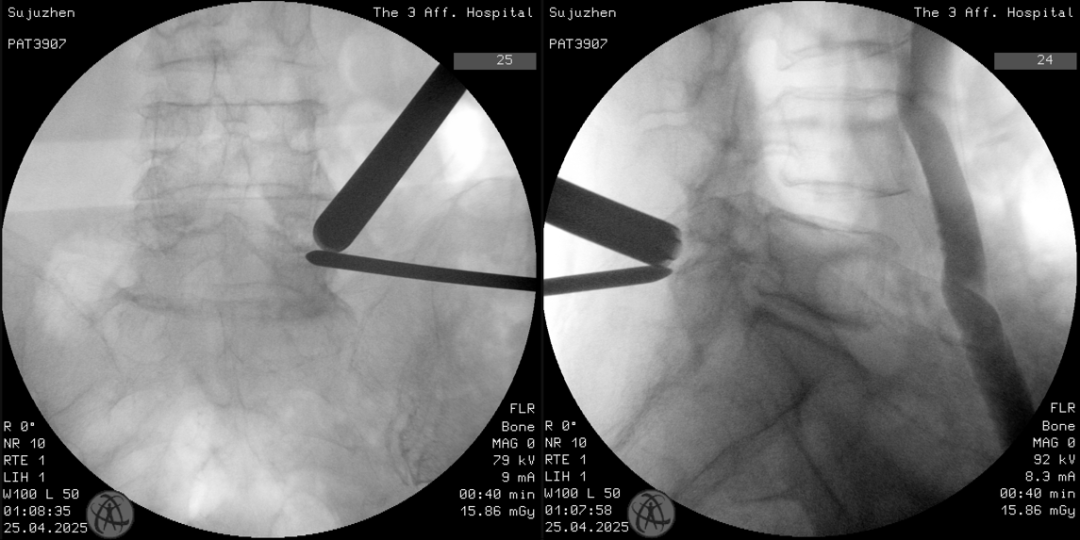

术中透视

针对这一复杂病情,结合患者身体状况,团队决定采用目前先进的微创技术——单侧双通道内镜技术(UBE)切除增生骨质,解除神经压迫。相较于传统开放手术,UBE仅需两个1厘米左右的切口,通过椎旁入路精准到达病灶,切除增生的右侧S1上关节突尖部,扩大椎间孔,既能彻底解除神经压迫,又最大限度保护脊柱稳定性。手术顺利完成,术后次日苏女士即感右下肢轻松,坐起吃饭30分钟也没有出现疼痛,“像卸下了千斤重担”。